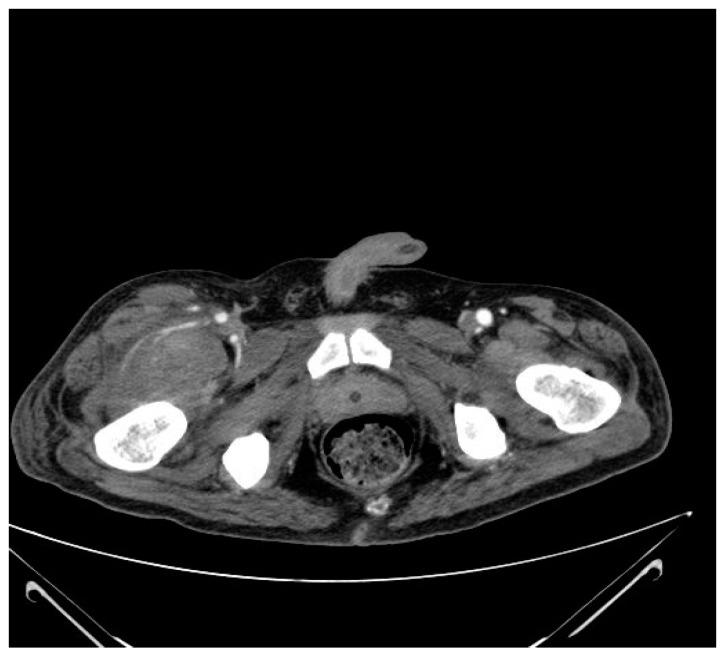

Spinal cord injuries (SCIs) are associated with a high risk of thromboembolic complications (VTE), despite the use of antithrombotic prophylaxis in the form of low-molecular-weight heparin (LMWH). The occurrence of VTE requires, as in other diseases, full-dose antithrombotic treatment. Herein, we describe seven cases of soft tissue hemorrhagic complications in the form of spontaneous intramuscular hematomas (SMHs) in patients after SCI undergoing rehabilitation. Four patients received anticoagulant therapy due to previously diagnosed deep vein thrombosis (DVT), and three patients received anticoagulant prophylaxis. None of the patients had a significant injury immediately before the hematoma appeared, and the only symptom was a sudden swelling of the limb without accompanying pain. The hematomas in all patients were treated conservatively. In three patients, significant decreases in hemoglobin were observed; in one patient, a blood transfusion was required for this reason. In all patients treated via anticoagulation, the anticoagulation treatment was modified at the time of diagnosis of the hematoma; in three patients, oral anticoagulants were changed to LMWH in a therapeutic dose, while in one patient, anticoagulant treatment was completely discontinued. Conclusions: Intramuscular hematomas are rare complications after SCI. Each sudden swelling of a limb requires ultrasound-based diagnostics. At the time of diagnosis of a hematoma, the level of hemoglobin and the size of the hematoma should be monitored. The treatment or anticoagulation prophylaxis should be modified if necessary.

脊髓损伤(SCI)与血栓栓塞并发症(VTE)的高风险相关,尽管采用了低分子量肝素(LMWH)形式的抗血栓预防措施。与其他疾病一样,VTE的发生需要全剂量抗血栓治疗。在此,我们描述了7例脊髓损伤患者在康复过程中出现的以自发性肌内血肿(SMH)形式的软组织出血并发症。4例患者因先前诊断为深静脉血栓形成(DVT)而接受抗凝治疗,3例患者接受抗凝预防。在血肿出现之前,所有患者均未遭受重大损伤,唯一症状是肢体突然肿胀且无伴随疼痛。所有患者的血肿均采用保守治疗。3例患者观察到血红蛋白显著下降;1例患者因此需要输血。在所有接受抗凝治疗的患者中,在诊断血肿时对抗凝治疗进行了调整;3例患者将口服抗凝剂改为治疗剂量的LMWH,1例患者完全停止抗凝治疗。结论:肌内血肿是脊髓损伤后罕见的并发症。肢体的每次突然肿胀都需要基于超声的诊断。在诊断血肿时,应监测血红蛋白水平和血肿大小。如有必要,应调整治疗或抗凝预防措施。